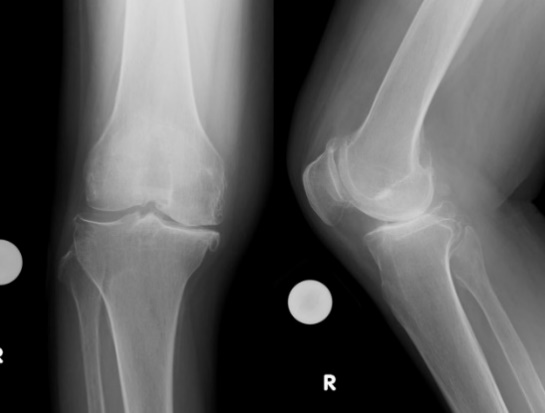

高位脛骨骨切り術 (high tibial osteotomy: HTO)

変形性膝関節症や大腿骨内顆骨壊死症などに適応があります。

脛骨の近位部を骨切りし、O脚に変形した下肢を軽度X脚に矯正し、荷重による負担を膝外側に移動することによって、膝内側の痛みを緩和する方法です。変形の程度によって開大式と閉鎖式骨切り術を使い分けております。